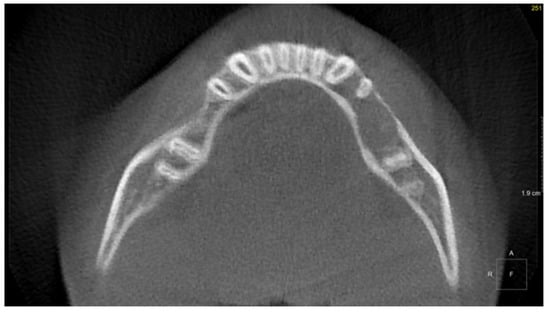

The 8-year-old patient was referred to the Children’s Dental Clinic because of trauma of front upper central incisors. Hypermobility of the left upper incisor with swelling and bloody petechiae of the upper lip were noticed. Because the periapical X-ray was inconclusive, a CBCT examination (NewTome 3G, 110 kV, 2 mA, 18 s) of the maxilla was performed to evaluate the possible presence of a fracture of either the root or the alveolar bone. CBCT ruled out the presence of a fracture in the front upper region but revealed the presence of a soft-tissue mass covering the area of the hard palate and extending into a maxillary sinus and a nasal cavity, which had dimensions of 25 × 25 × 20 mm (Figure 4). Clinical re-examination showed a dome-shaped enlargement of the palate extending from the midline to the palatal aspect of tooth 26 (FDI). A non-shifting mass of medium consistency was covered with pale, normal-looking soft tissue. The adjacent teeth showed normal vitality and mobility, and no palpable lymphadenopathy was observed. The patient underwent an open biopsy of the palatal mass. Histopathological examination revealed a high-grade B-cell lymphoma (Figure 5). The patient then underwent an extent-of-disease evaluation. MRI examination in the TSE, T1 and T2, and fluid-attenuated inversion recovery (FLAIR DWI) sequences was performed. An increase in signal intensity with thickening of the palatal mucosa on the left side was observed with a blurred pattern of the alveolar bone in the region of teeth 26 and 27 and post-contrast enhancement (Figure 6). A positron emission tomography (PET-CT) examination did not reveal the presence of other outbreaks of the disease in the regions of the head and neck, abdominal cavity, pelvis, or skeleton. On the basis of the results of the extended examination, the patient was classified into stage III and the low/intermediate treatment group according to the EICNHL-COG Inter-B-NHL-2010 protocol, and a 7-day cytoreductive prephase COP was initiated. Subsequently, the patient completed two cycles of COPADM and two CYM cycles without Rituximab. Because of an unsatisfactory response to the chemotherapy, supplementary treatment was introduced with two additional cycles of R-CYVE (Rituximab, Cytarabine, and Etoposide). Finally, the patient responded well to the therapy, and remission was achieved. Currently, seven years after the initial diagnosis, he undergoes regular check-ups, including dental examinations. The intraoral lesion resolved completely because of chemotherapy, and no surgical treatment was performed.

Figure 4. Patient, 8 y.o.: Coronal, sagittal, and axial reconstruction from CBCT examination. Soft-tissue mass covering the area of the hard palate and extending into a maxillary sinus and a nasal cavity.